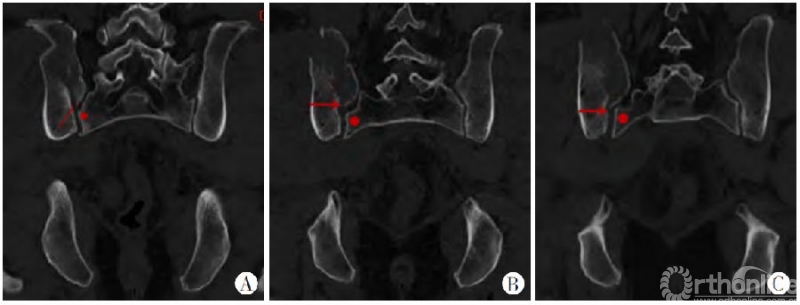

图8 A~C.横断面特点:横断面由近及远各层面显示新月形骨折内板骨折线(红色箭头所指)起自骶骨侧嵴(红色圆点),基本垂直骶髂关节面走行,也随层面不断变化,骨折线起点在各层面均与骶骨侧嵴紧密相关,骶髂关节被累及范围变异较斜形骨折线小

图9 A~C.冠状位表现:新月形骨折内板骨折线(红箭头所指)与骶骨侧嵴(红色圆点所指)密切相关,冠状位骶髂关节累及范围随层面变异程度较横断面轻

冠状位表现可以作为新月形骨折病理解剖学分型的一个重要参考。